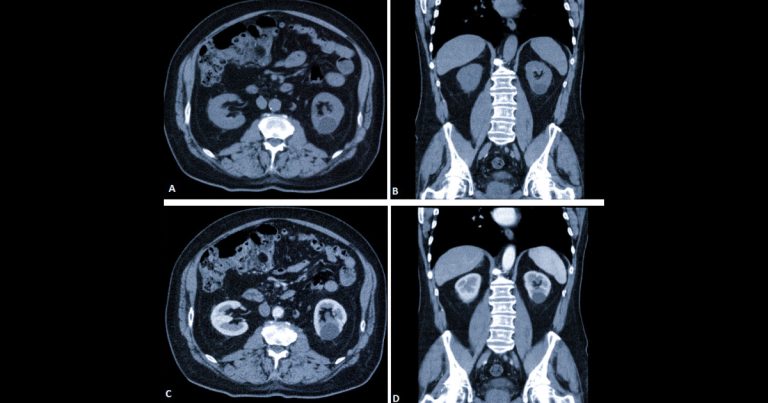

Підготовка до КТ черевної порожнини: дієта та «голодний» режим

Статті Автор: Ан-Сі-Тек Тетяна

Комп’ютерна томографія (КТ) черевної порожнини — це швидкий і точний спосіб оцінити стан внутрішніх органів. Але якість результату залежить не лише від апарата та лікаря, а…

КТ черевної порожнини: ознаки гострого апендициту та панкреатиту

Гострий біль у животі — одна з найчастіших причин звернення по медичну допомогу. У таких ситуаціях важливо швидко встановити причину, адже деякі стани потребують невідкладного лікування.…

МРТ черевної порожнини: що «бачить» апарат у печінці, підшлунковій та нирках

Статті Автор: Alla Kovshova

Магнітно-резонансна томографія (МРТ) черевної порожнини — це сучасний і безпечний метод обстеження, який дозволяє детально оцінити стан внутрішніх органів без болю та опромінення. Для пацієнта це…

КТ-ентерографія: діагностика хвороби Крона та пухлин кишечника

Захворювання тонкого кишечника часто залишаються «сліпою зоною» для стандартної діагностики. Через анатомічні особливості цей відділ складно оцінити за допомогою звичайної ендоскопії чи УЗД. Саме тому у…

Віртуальна колоноскопія: як перевірити кишечник без дискомфорту?

Здоров’я кишечника — одна з ключових складових загального самопочуття. Водночас багато людей відкладають обстеження через страх перед дискомфортом класичної колоноскопії. Сучасна альтернатива — віртуальна колоноскопія (КТ-колонографія),…